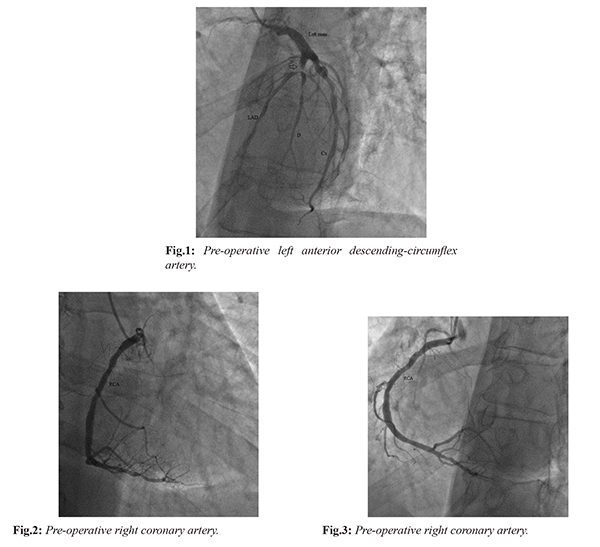

On his physical examination, body temperature was 36.7ºC, arterial blood pressure was 130/70 mmHg, respiratory rate was 16/min, pulse rate was 83/min, and oxygen saturation by pulse-oximeter was 90-93%. Heart sound was rhythmic with normal S1-S2 without abnormal sound or murmur. It was determined that each hemi-thorax moves symmetrically, and no rale or rhoncus was heard. Abdominal examination revealed no distension, rebound or tenderness. Peripheral pulses were palpable. With regard to the cardiac markers in the laboratory analyses, troponin-I was normal and CK-MB was mildly elevated (28 mmol/L; reference range: 0-25 mmol/L). On his electrocardiography, negative T waves were detected in the anterior leads. While his trans-thoracic echocardiography performed in the polyclinic demonstrated no valvular pathology, decreased ventricular systolic functions were determined. The patient was admitted to the coronary angiography (CAG) laboratory for percutaneous coronary intervention. After CAG, stenosis greater than 75% was detected in the branching point of proximal and diagonal left anterior descending (LAD) and in the circumflex (Cx) coronary artery [Fig.1], whereas right coronary artery had stenosis not requiring surgery [Fig.2,3].